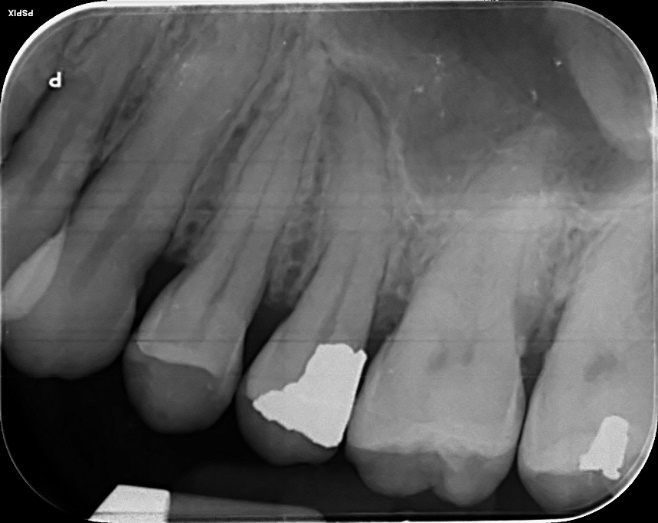

Upper Premolar and Molar root canal treatment and restoration